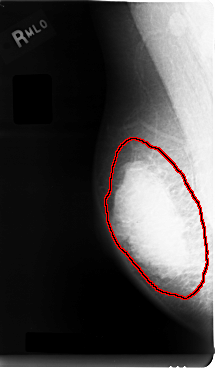

C_0005_1.RIGHT_MLO

RIGHT_MLO LINES 4784 PIXELS_PER_LINE 2784 BITS_PER_PIXEL 12 RESOLUTION 50 OVERLAY

FILE: C_0005_1.RIGHT_MLO.OVERLAY

TOTAL_ABNORMALITIES 1

ABNORMALITY 1

LESION_TYPE MASS SHAPE LOBULATED MARGINS MICROLOBULATED

ASSESSMENT 5

SUBTLETY 5

PATHOLOGY MALIGNANT

TOTAL_OUTLINES 1

BOUNDARY